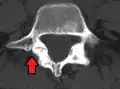

Isthmic anterolisthesis is where there is a defect in the pars interarticularis (spondylolysis).[15] It is the most common form of spondylolisthesis; also called spondylolytic spondylolisthesis, it occurs with a reported prevalence of 5–7 percent in the US population. A slip or fracture of the intravertebral joint is usually acquired between the ages of 6 and 16 years, but remains unnoticed until adulthood. Roughly 90 percent of these isthmic slips are low-grade (less than 50 percent slip) and 10 percent are high-grade (greater than 50 percent slip).[13] It is divided into three subtypes:[16]